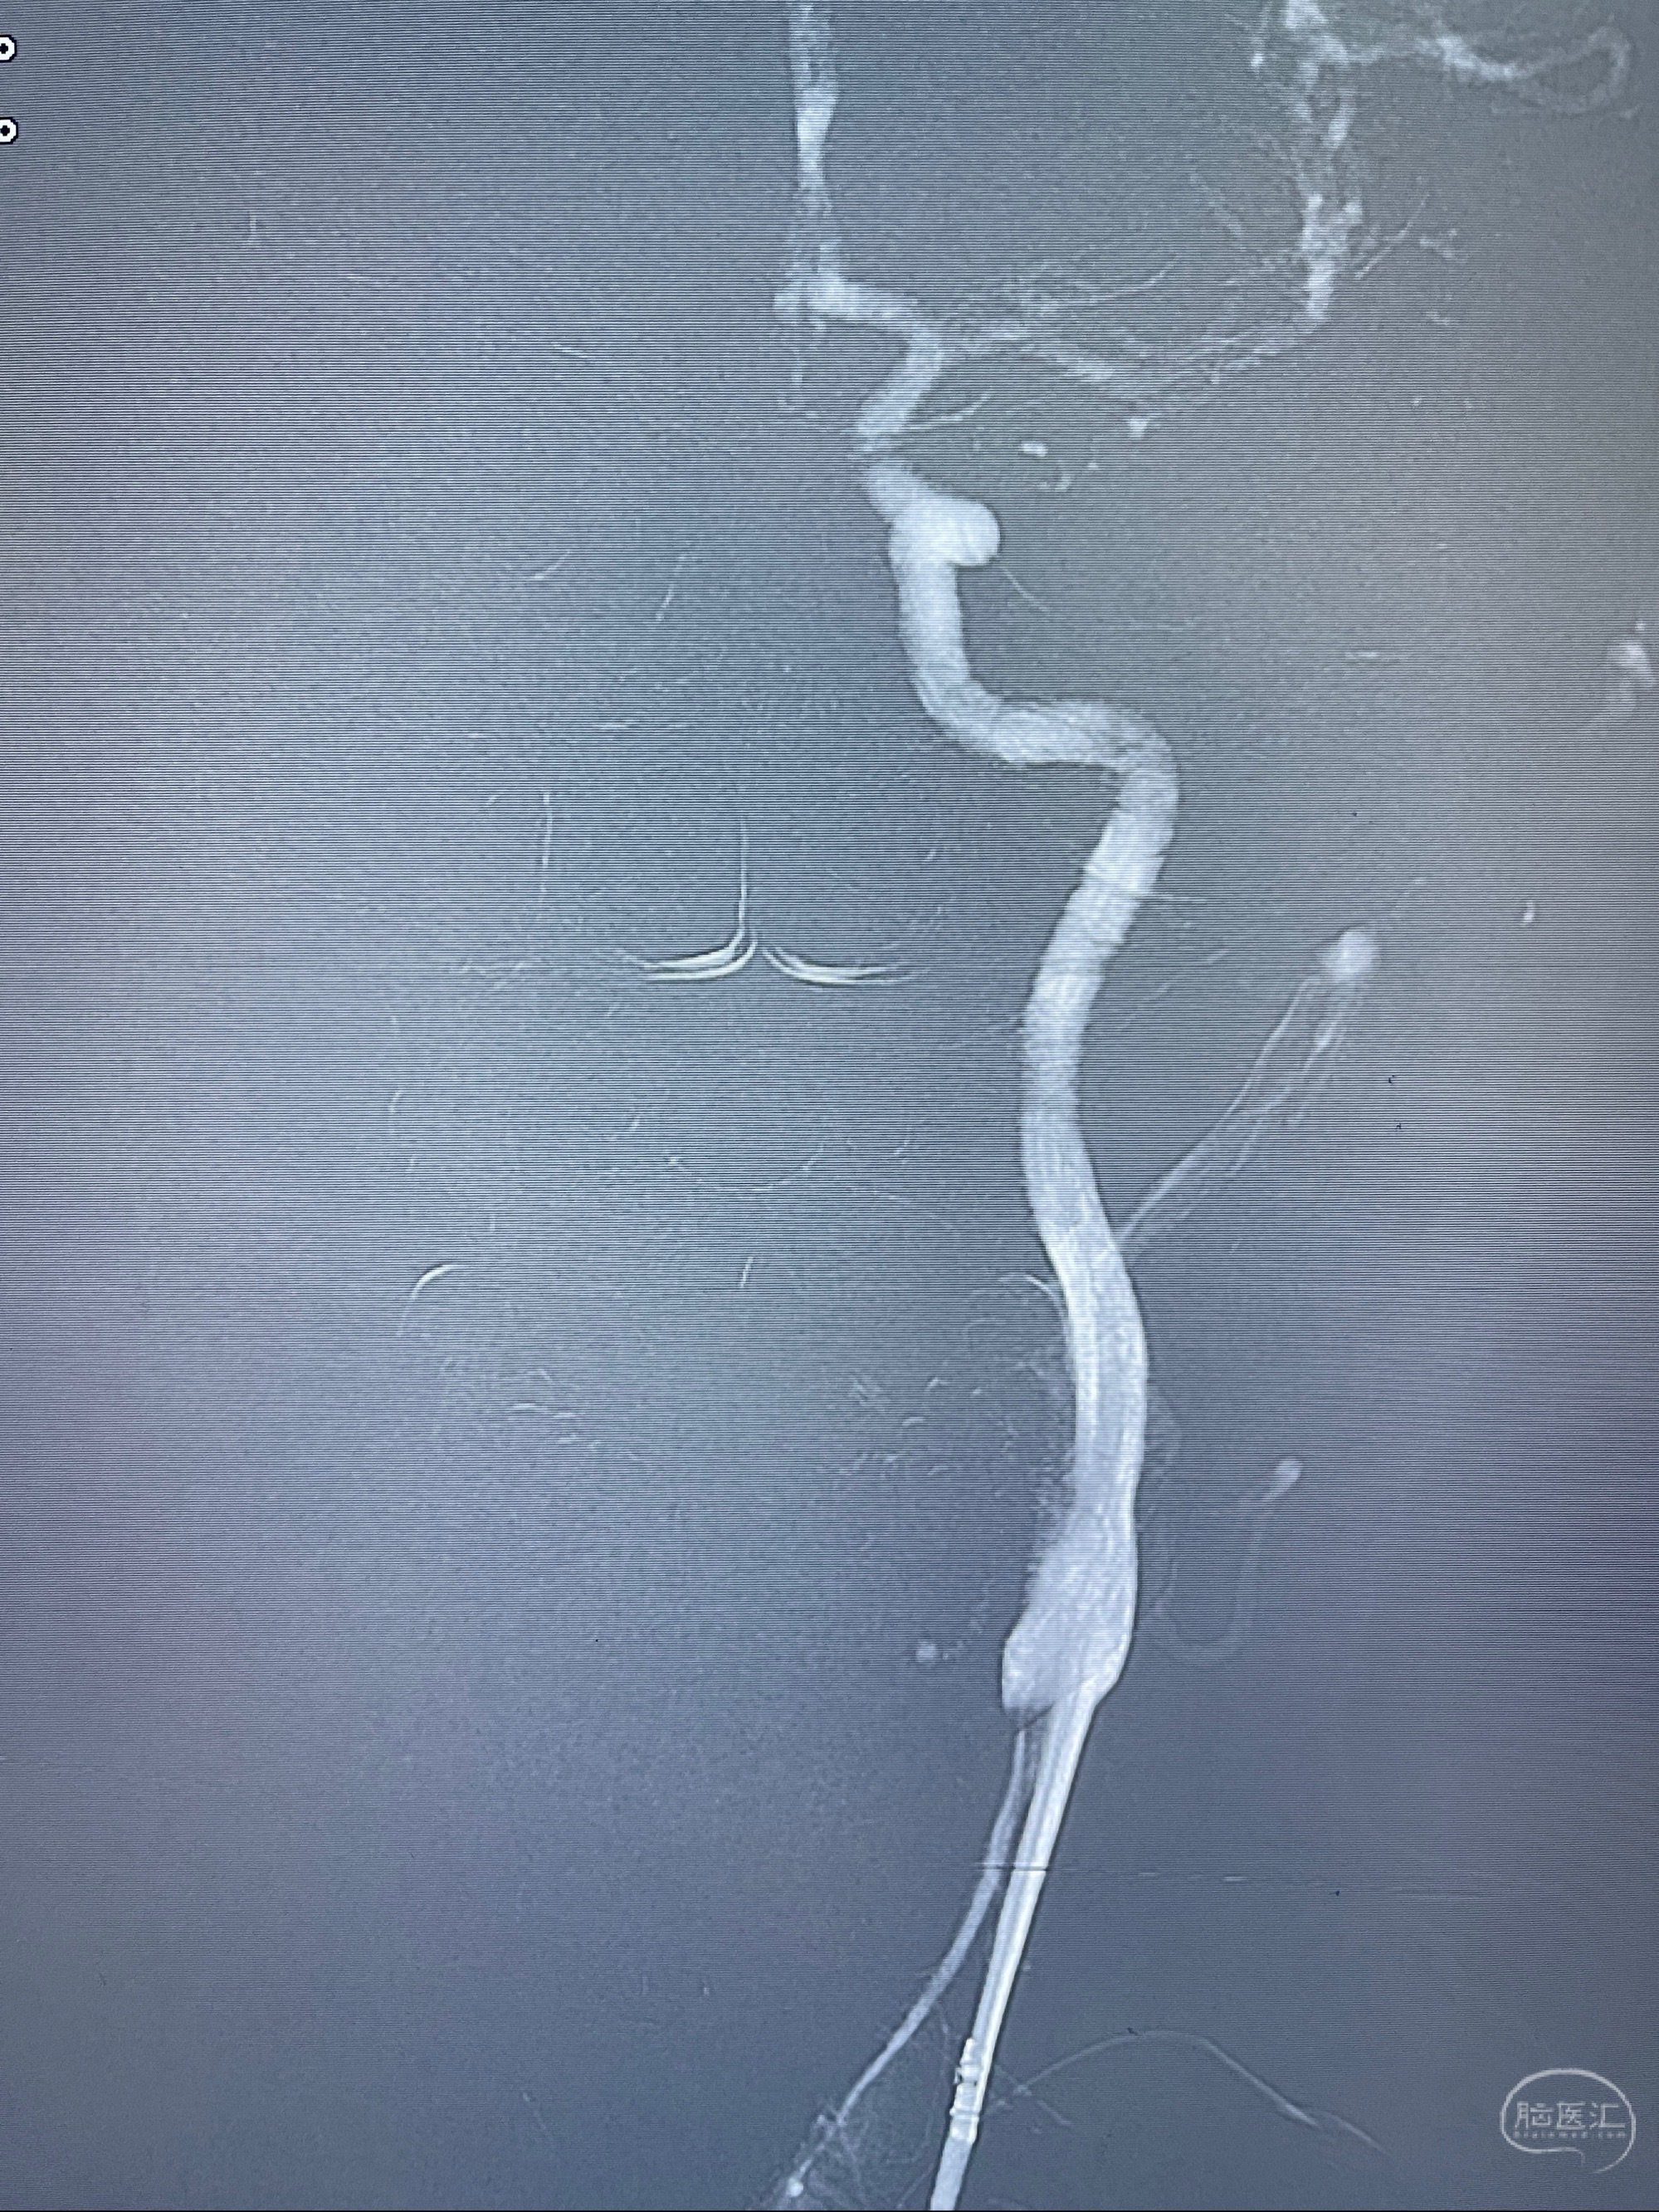

麻醉苏醒佳,遵嘱动作

术后即刻CT